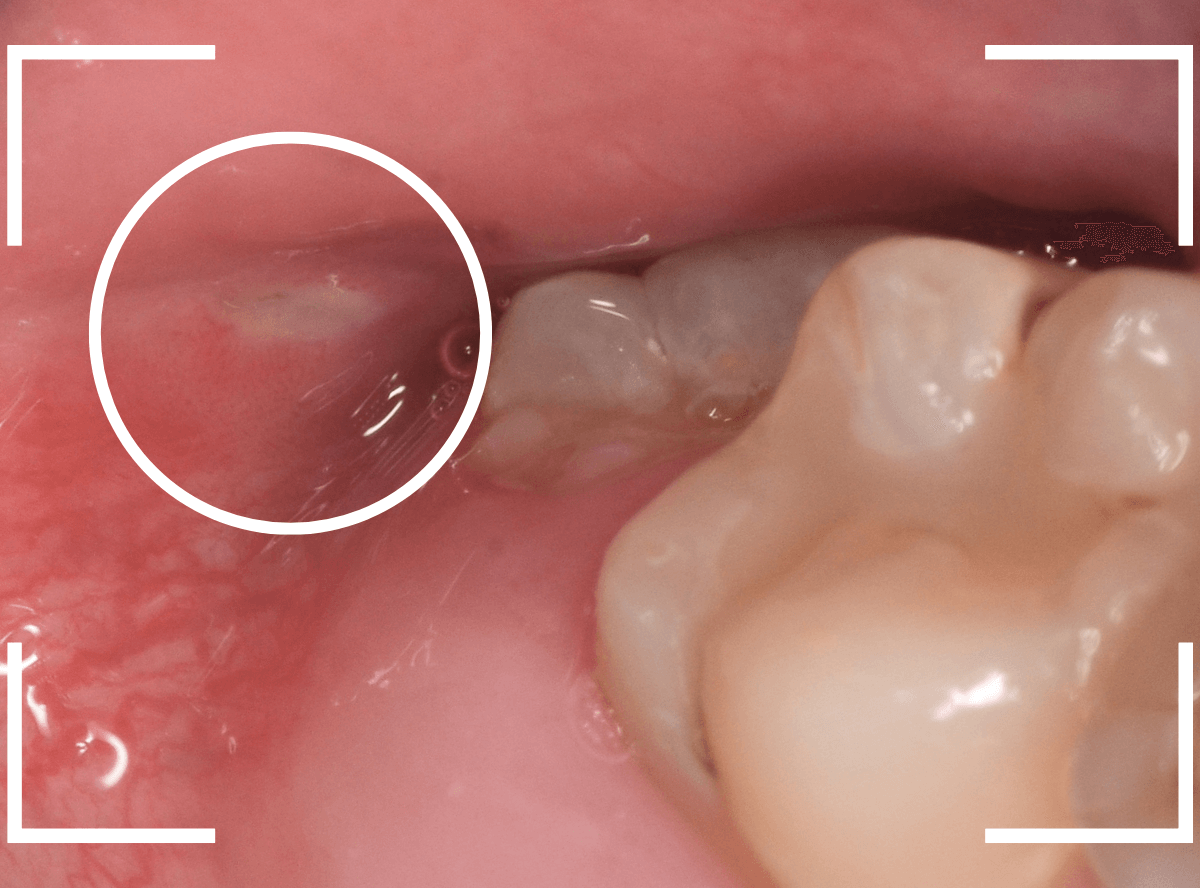

このようなおやしらず、あなたはありませんか?